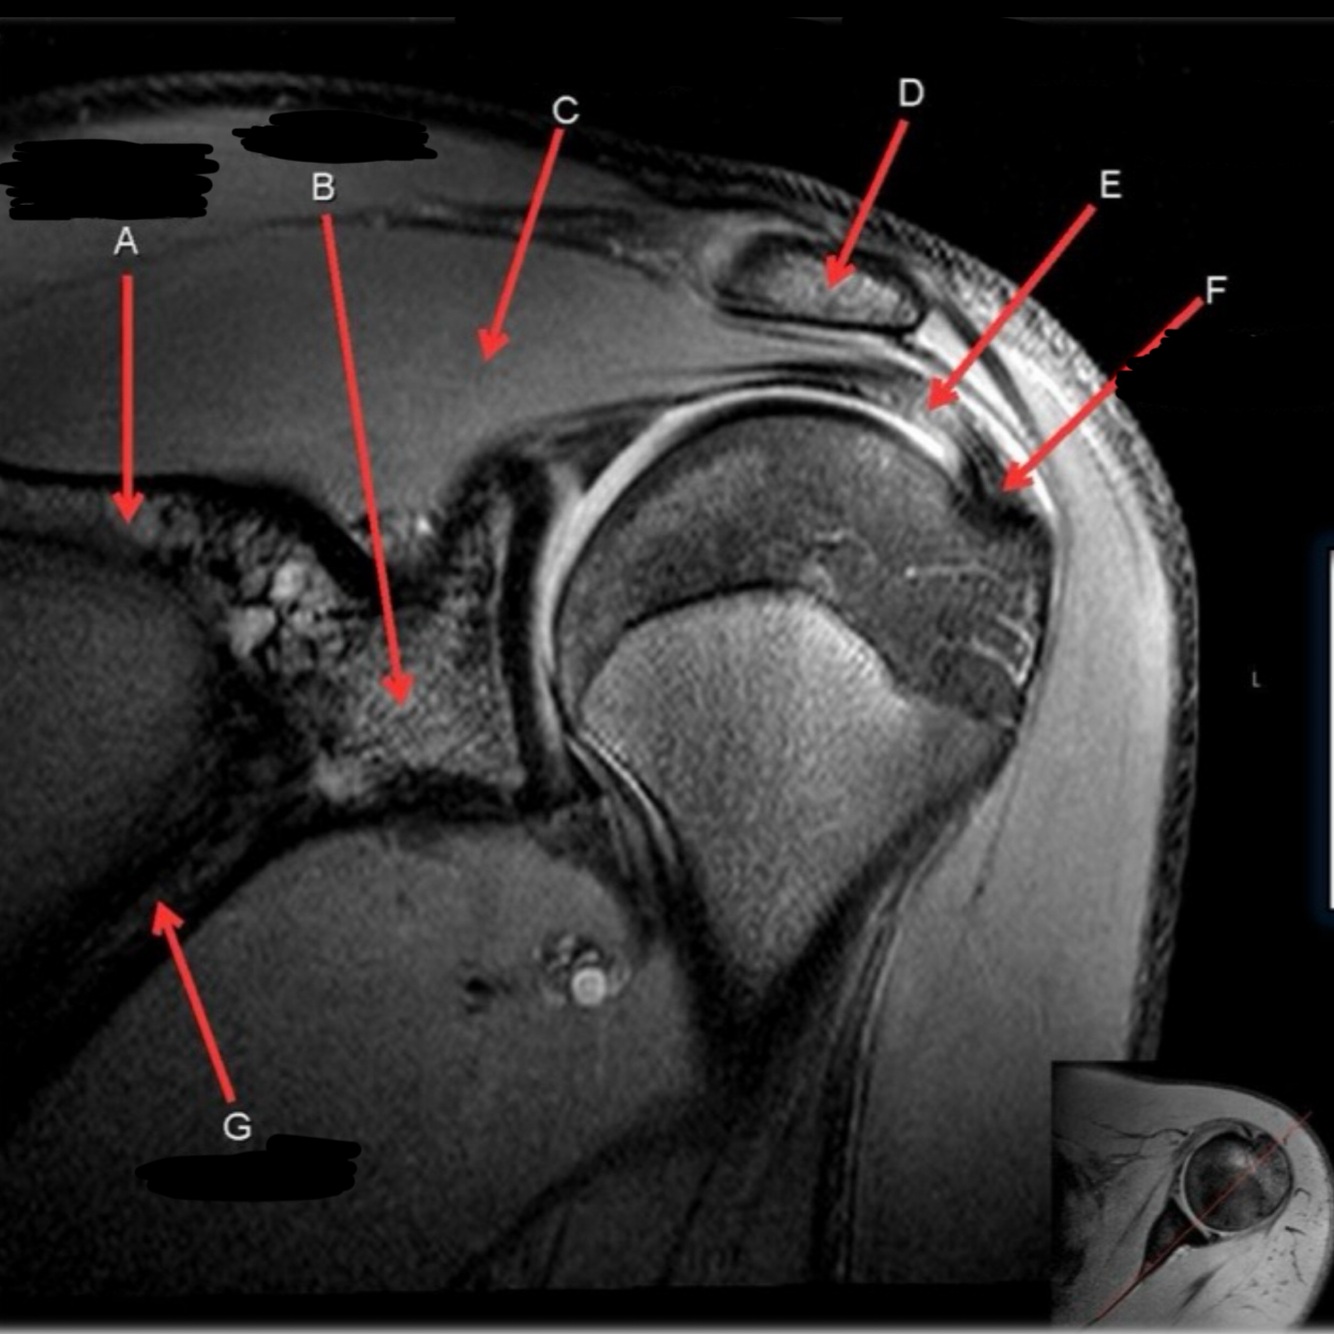

25

What is letter C?

SUPRASPINATUS MUSCLE

26

What is letter D?

ACROMION

27

What is letter E?

SUPRASPINATUS TENDON

28

GREATER TUBEROSITY

29

What is letter G

SCAPULA

30

What is letter A?

CLAVICLE

31

What is letter B?

AC JOINT

32